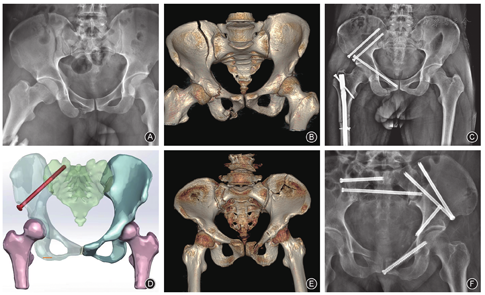

Young-Burgess根据损伤机制将骨盆骨折分为四型,其中LC-Ⅱ型为侧方挤压暴力所致的骨盆新月样骨折。临床上将治疗此类骨折而采用的通道称为LC-Ⅱ通道。

Day等[8]将骨盆新月样骨折分为三种亚型并提出了相应的治疗方案。其中Ⅰ型为经髂骨不超过骶髂关节前1/3骨折脱位并伴巨大的半月形骨块,可采取前方入路跨骶髂关节钢板固定;Ⅱ型为经髂骨骶髂关节中1/3骨折脱位并伴中等大小的半月形骨块,可选择后方入路中和钢板及加压螺钉固定;Ⅲ型为经髂骨骶髂关节后1/3骨折脱位并伴较小的半月形骨块,可借助骶髂螺钉固定[6,7]。Gehlert等[9]认为DayⅢ型骨折系骨盆旋转或垂直不稳定型损伤,其髂骨后方的骨折形态决定内固定方式的选择。目前认为,在处理骨盆前环损伤的基础上,髂嵴边缘钢板结合LC-Ⅱ螺钉顺行或逆行置入,必要时辅以骶髂螺钉固定是DayⅢ型骨折治疗的常规方法。

LC-Ⅱ通道可用于治疗大部分骨盆新月样骨折、髂骨翼及中高位髋臼前柱骨折。患者仰卧位或俯卧位,通过泪滴位、髂骨正位、髂骨斜位以及LC-Ⅱ长轴位透视影像判断螺钉位置和长度后,从髂前下棘至髂后上棘或反其道由后向前设计固定方式。LC-Ⅱ通道的髂前下棘处也是骨盆前环内固定支架(internal fixator,INFIX)的螺钉入点,术中应注意保护股外侧皮神经;其髂后上棘处为髂腰内固定的髂骨钉入点,钉尾常可于皮下触及。该通道全长平均136.2 mm,螺钉须走行于髂骨内外板之间,与骨盆后环应力传导途径基本一致。

经LC-Ⅱ通道的改良骶髂螺钉,即螺钉大部分经LC-Ⅱ通道经骶髂关节与骶骨固定(图2)。其中位于S1的骶髂螺钉入点应外移至髂前下棘后外侧20~30 mm及臀中肌柱的前缘处,出点则接近于S1关节突的外下缘。主要用于辅助治疗累及骶髂关节的骨盆新月样骨折、骶骨近端严重畸形无S1骶髂螺钉安全通道、老年脆性骨折或协同骨盆复位机器人的通道螺钉固定。此外,改良的骶髂螺钉也可通过调整其出入点的位置而形成多种固定方式[10,11]。